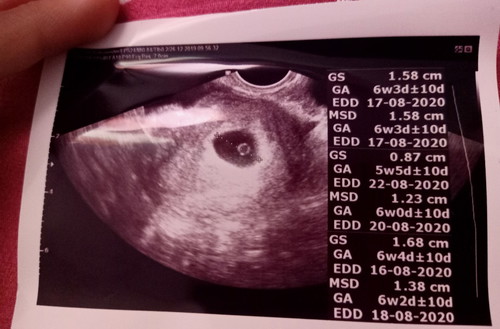

สวัสดีค่ะแม่ๆมีเรื่องจะปรึกษาดิฉันตั้งครรภ์ได้7สัปดาห์กับ4วันแต่ผลอัลตราซาวด์ออกมาว่าพบถุงตั้งไข่แดงแบบนี้ถือว่าปกติไหมคะเพราะผลอัลตราซาวด์ของพี่อีกคนที่ตั้งครรภ์ได้7สัปดาห์เท่าๆกันยังเห็นหัวใจแล้วแต่ของดิฉันไม่เห็น แต่หมอที่อัลตราซาวด์ก็บอกว่าปกติ แต่ดอฉันแค่สงสัยๆค่ะ กลัวว่าจะผิดปกติหรือมีพัฒนาการช้าหรือป่าว